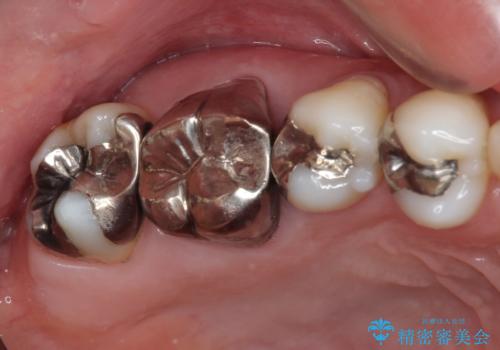

痛む奥歯 セラミッククラウンによるむし歯治療